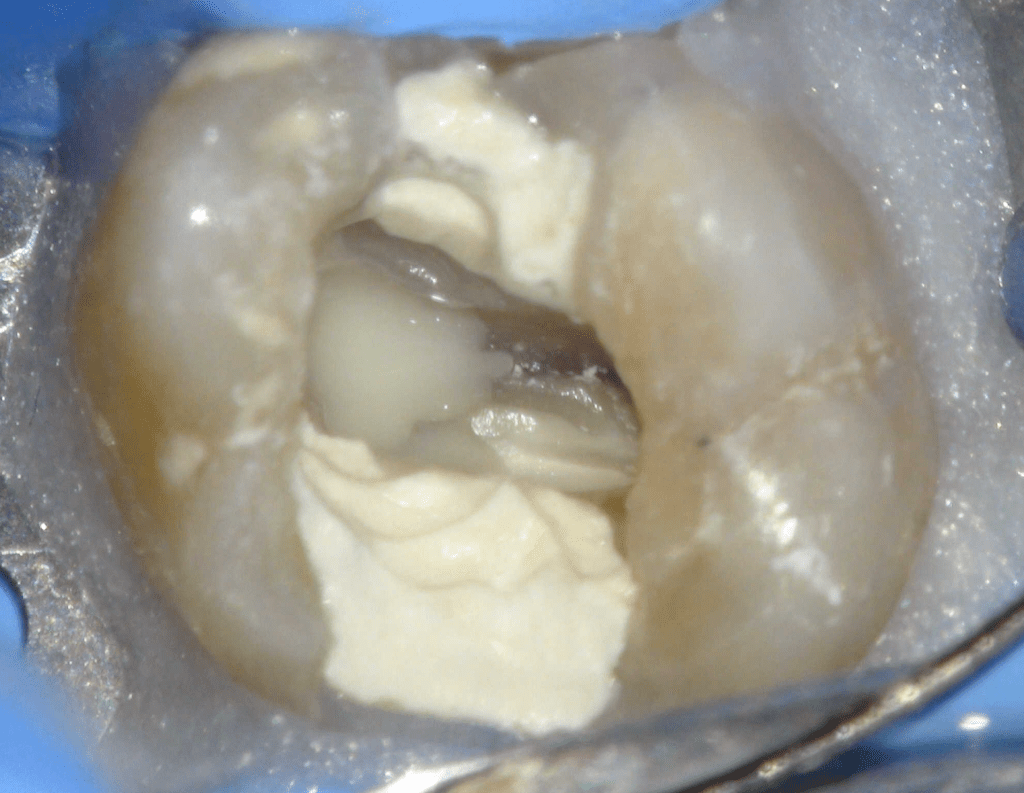

Reconstrucción preendodóntica

Molar superior

Reco palatina

Reco pared vesticular

Reco pre-endo gingivectomái, pared yuxtaosea

Reco pre-endo, molar inferior

Reco preendo + 4 conductos molar superior

Reco preendo + gingivectomía

Reco preendo, 2o Molar superior

Reconstrucción debajo de puente